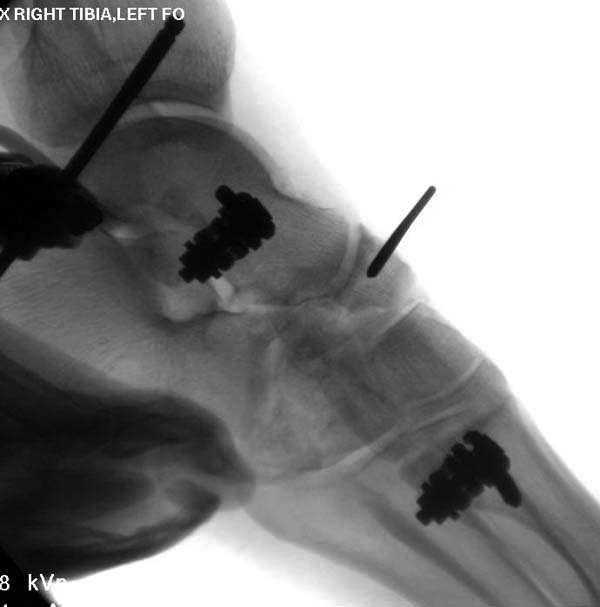

На рентгенограммах – классический перелом пилона (C3). Современный подходы к лечению таких повреждений – двухэтапный протокол. Сначала - дистракционный аппарат (стержневой или спицевой) в течение двух недель. На этом этапе следуют принципу: повреждения мягких тканей – всё, повреждения костей – ничто. Никаких оперативных вмешательств в этот период выполнять не рекомендуется (несмотря на «удовлетворительное состояние» мягких тканей). КТ необходимо выполнять в дистракционном аппарате. Будет более понятная картина, позволяющая спланировать ход последующей открытой репозиции и остеосинтеза. Сдержано относятся к первичному артродезированию. Многое зависит от опыта хирурга и технического оснащения. Ход оперативного вмешательства можно будет обсудить после выполнения рентгенограмм и КТ в дистракционном аппарате. Более информативна КТ со срезами в корональной плоскости. Результат при прочих равных условиях находится в прямой зависимости от точности репозиции суставной поверхности. Долгосрочный прогноз, как правило, плохой. В 60-70% случаев через пять лет всё заканчивается артродезом.

Лечение можно разделить на 2 этапа. 1ое остеосинтез малоберцовой кости из задне-наружного доступа после дистракции. Попытаться выполнить чрезкожно репозицию и остеосинтез простого перелома метафиза большеберцовой кости стягивающим винтом. фиксация аппаратом внешей фиксации. 2ое. Через 10-14 дней, при хорошем состоянии мягких тканей ORIF, возможно даже из двух доступов, накостный остеосинтез с костной пластикой. Если перелом метафиза неотрепонирован, то следует начать с него. Затем либо задневнутренние либо наружные отделы большеберцовой кости. Следует начать с того, что проще. Временно фиксировать спицами. Затем стягивающими винтами. Остеосинтез двумя пластинами. Лучше всего Lобразная LCP спереди, медиально метафизарная LCP. Пластины проксимально должны выходить за место перелома минимум на 4 отверстия.Желательно проводить пластины подкожно, а фиксировать через небольшие разрезы. Если нет пластин, то аппарат Илизарова. Принципы тебе. Если время упущенно и состояние мягких тканей очень плохое, то аппарат внешней фиксации с хорошей дистракцией. На представленных снимках дистракция недостаточна. можно чтото попытаться закрыто и ждать.

1. Представленные картинки не очень информативны, точнее совершенно неинформативны, так как выполнены в условиях отсутствия вытяжения. Несмотря на формально наложенное скелетное вытяжение, при помещении на томограф вытяжение ведь пришлось снять? Поэтому и информации от этого исследования - ноль. В этой связи есть смысл сделать обычные рентгенограммы на скелетном вытяжении. Хотя бы примерно будет ясна степень повреждения и потенциальная тенденция к восстановлению. На этом этапе уже можно будет примерно ответить на вопрос - что делать. В смысле артродез или пытаться сохранить сустав.

Ещё несколько слов по поводу стратегии и тактики лечения обсуждаемого перелома. Из всех переломов пилона С3, переломы с одновременной деструкций эпифиза, дистального метафиза и нижней трети диафиза большеберцовой кости являются наиболее проблемными при выборе способа финального остеосинтеза. К общепринятому способу остеосинтеза переломов пилона пластинками по медиальной либо латеральной поверхности большеберцовой кости в таких случаях следует относиться критически. Имплантация необходимой длины пластинок (иногда до 20-25 см) требует такой же длины разрезов кожи и мягких тканей, отслоение надкостницы, что ставит на грань разумного их применение из-за возникающих впоследствии тяжёлых осложнений. MIPO (Minimally Invasive Plate Osteosynthesis) крайне сложно реализовать на практике из-за необходимости точной репозиции отломков, имеющих суставную поверхность на уровне эпифиза, и недопустимости угловых деформаций на уровне метафиза и диафиза. Поэтому в последнее время всё большую популярность приобретает комбинированный способ финального остеосинтеза. Если ставить перед собой задачу сохранения сустава, надо исходить из понимания, что дистракция и лигаментотаксис в большинстве случаев переломов пилона не обеспечат репозицию отломков, образующих суставную поверхность. Открытая репозиция неизбежна, так как почти всегда имеются отломки с суставной поверхностью «вбитые» в метафиз. Но открытая репозиция из разрезов длиной 5-6 см должна применяться только для репозиции и фиксации между собой отломков, образующих суставную поверхность. Для этих целей применяются спицы и спонгиозные винты диаметром до 4,5 мм. Реконструированный таким образом дистальный эпиметафиз и проксимальный отломок большеберцовой кости фиксируются спицевым или стержневым аппаратом.